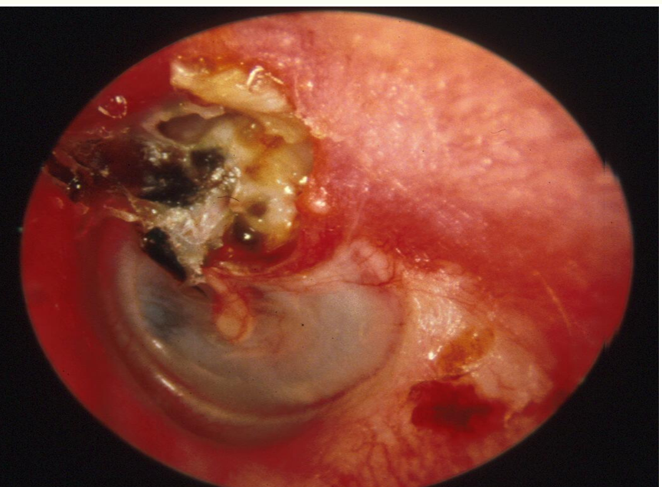

What’s seen on otoscopy in cholesteatoma?

‘attic crust’ - seen in the uppermost part of the ear drum